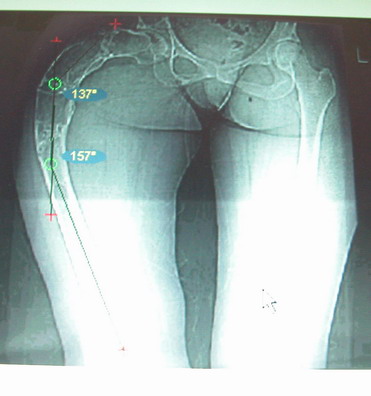

На мой взгляд, для того, чтобы правильно исправить данную деформацию, необходимо обследование больного, которое должно включить в себя, помимо осмотра: 1. Рентгенограммы ( передне-задние и боковые)нижних конечностей на всю длину стоя . 2. Компьютерная томография для измерения длины нижних конечностей. 3. Комьютерная томография тазобедоенных, коленных и голеностопных суставов для измерения углов антеверсии тазобедренных суставов и ротации голеней. Это тот минимум, который должен входить в предоперационное обследование каждого больного с тяжёлыми формами деформаций конечностей.

Поскольку в данном случае имеется дело с довольно большой деформацией с укорочением, одномоментная её устранение с внутренней фиксацией, чревато с одной стороны неправильной коррекцией, с другой, нейроваскулярными осложнениями.

Моё мнение, что двойная остеотомия бедра с аппаратом Илизарова + Гексаподный механизм, или Тэйлора, В данной ситуации является методом выбора. Я очень извеняюсь за качество прилагаемых снимков, в которых я постарался отразить разницу междe одной и двумя остеотомиями бедра.